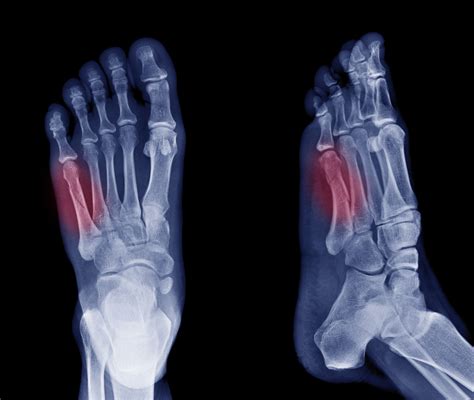

Diagnosing a Fifth Metatarsal Fracture

Diagnosing a Fifth Metatarsal Fracture typically involves a combination of physical examination and imaging tests. The diagnostic process may include:

• Physical Examination: A healthcare provider will examine the foot, checking for swelling, tenderness, and deformity.

• X-Rays: X-rays are the primary imaging tool used to confirm the presence and location of the fracture.

• CT Scans or MRIs: In some cases, more detailed imaging such as CT scans or MRIs may be required to assess the extent of the fracture and plan treatment.